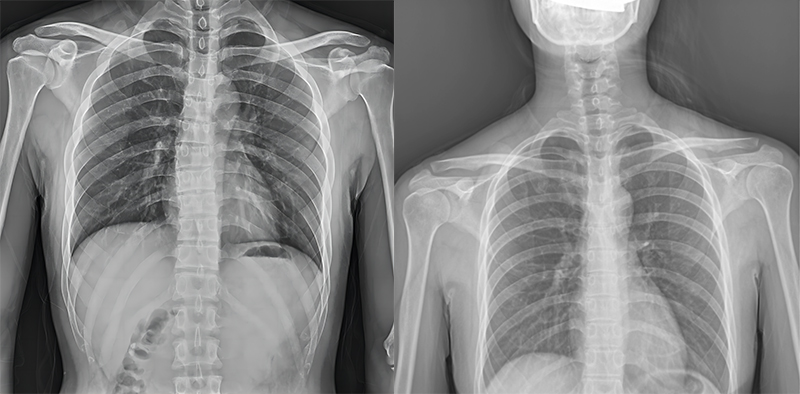

百微米DR與普通像素尺寸DR的影像對(duì)比

以胸部攝影為例,通過(guò)對(duì)比百微米大平板與普通像素尺寸平板的影像,可以看到百微米影像對(duì)比度適中,圖像清晰度更高,成像細(xì)節(jié)更加豐富。在胸部影像顯示中肺門影結(jié)構(gòu)、肺紋理等細(xì)節(jié)展示更清楚,兩側(cè)膈肌邊緣、心臟、縱隔邊緣清晰銳利顯示,在影像中都可以清晰地顯示胸部細(xì)微結(jié)構(gòu),滿足臨床診斷要求。